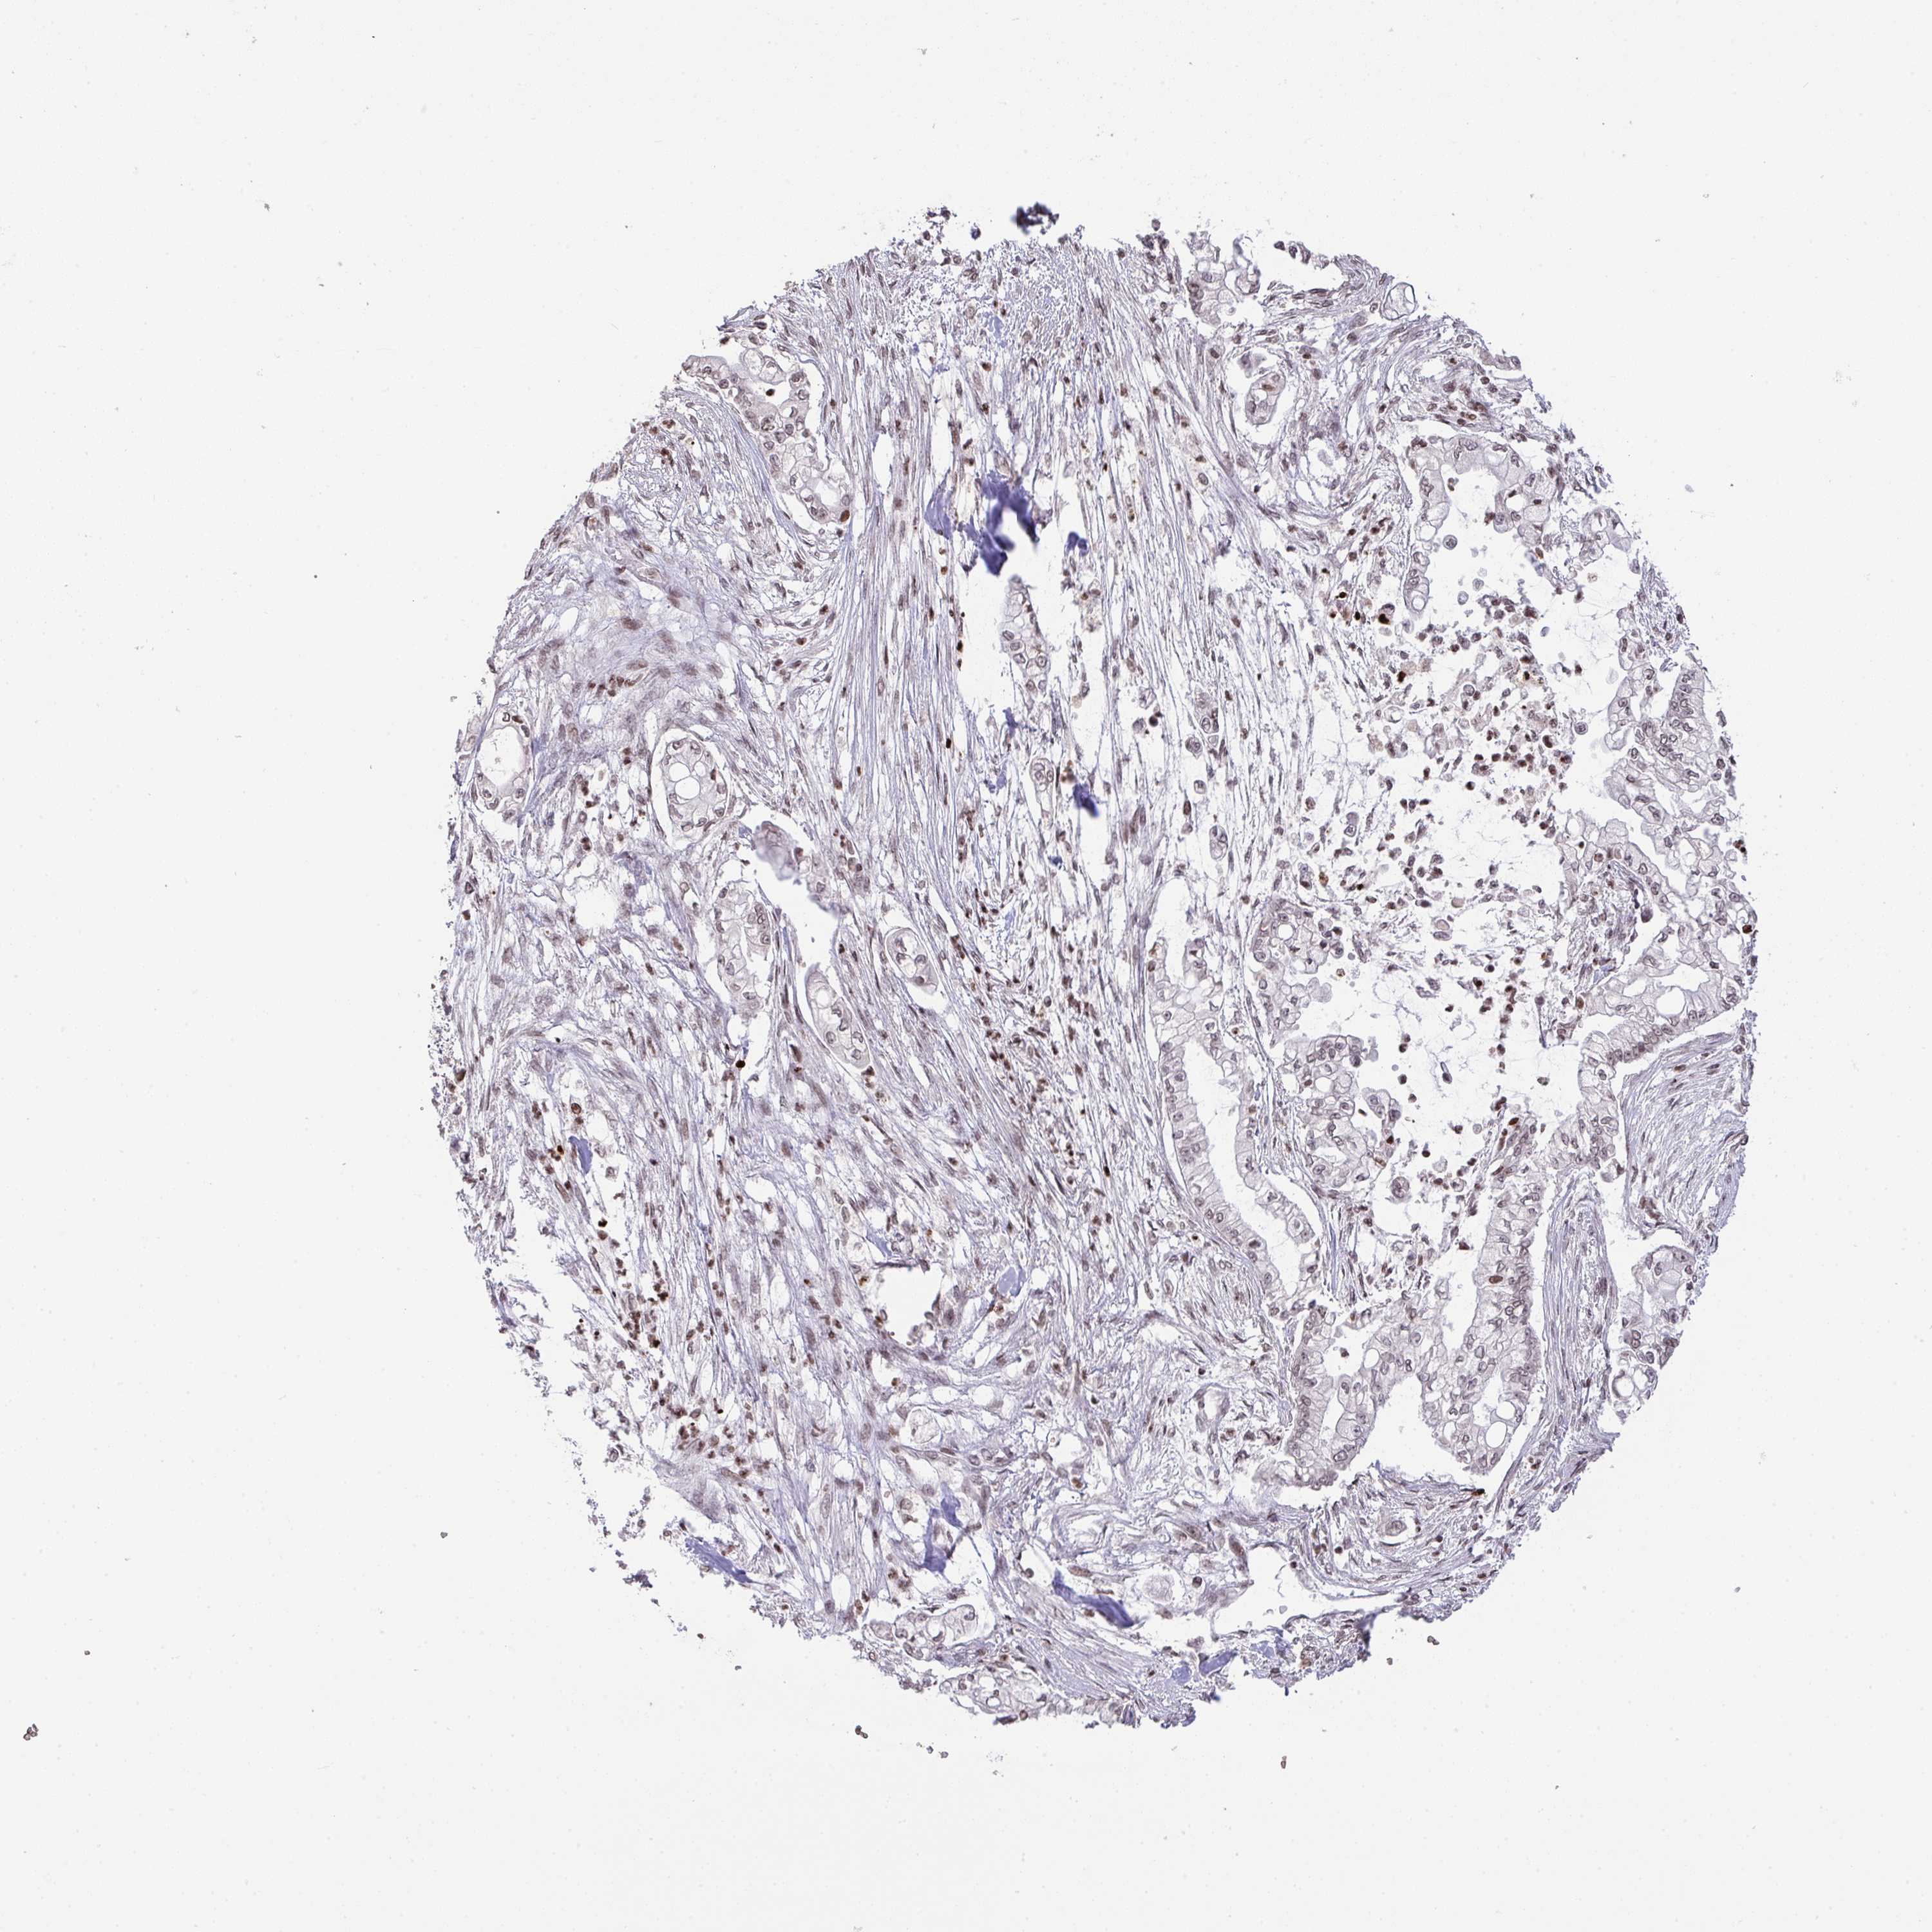

PANCREATIC CANCER - Protein expressioni

A mouse-over function shows sample information and annotation data. Click on an image to view it in a full screen mode. Samples can be filtered based on level of antibody staining by selecting one or several of the following categories: high, medium, low and not detected. The assay and annotation is described here.

Note that samples used for immunohistochemistry by the Human Protein Atlas do not correspond to samples in the TCGA dataset.

Antibody stainingi

Antibody staining in the annotated cell types in the current human tissue is reported as not detected, low, medium, or high, based on conventional immunohistochemistry profiling in selected tissues. This score is based on the combination of the staining intensity and fraction of stained cells.

Each image is clickable and will lead to virtual microscopy that enables deeper exploration of all samples and also displays staining intensity scores, fraction scores and subcellular localization as well as patient and tissue information for each sample.

Antibody HPA059850

Staining

High

Medium

Low

Not detected

Intensity

Strong

Moderate

Weak

Negative

Quantity

>75%

75%-25%

<25%

None

Location

Nuclear

Cytoplasmic/membranous

Cytoplasmic/membranous,nuclear

Adenocarcinoma, NOS